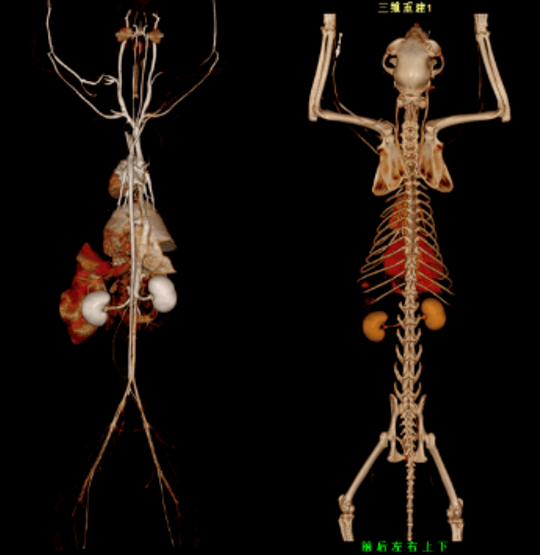

VetCare CT | 16 & 32 slices

VetCare CT series incorporate an entirely digital integrated ScintiStar detector, which was solely developed by MinFound, from material to the whole structure design, based on the technical know-how of our skilled scientific team. The system produces high-resolution images with a low radiation dose and an excellent signal-to-noise ratio.